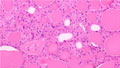

- (7)Follicular adenoma of the thyroid

Macroscopic findings. Cut surface reveals relatively well-circumscribed, white-yellowish, nodule with fibrous capsule (arrows).